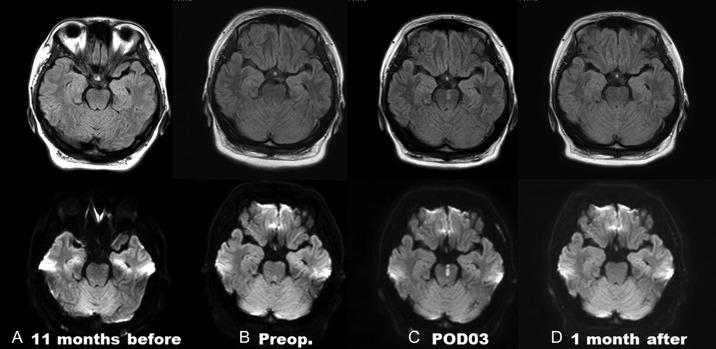

A 32-year-old pregnant woman in her 39th week of pregnancy presented at the emergency room complaining of sudden-onset dizziness with gaze disturbance and was admitted to our hospital. Her past medical history included hypertension, diabetes mellitus and infarction in the right medulla oblongata 18 months prior to this event. Magnetic resonance (MR) angiography showed multiple irregular stenosis of the intracranial arterial system. Although MR images revealed no fresh ischemic or hemorrhagic lesions, she was diagnosed with reversible cerebral vasoconstriction syndrome (RVCS) associated with pregnancy. Cesarean section immediately resolved the headache-free ischemic RCVS. The postpartum course of the patient was uneventful as well as that of her baby. Follow-up MR angiography showed improvement of intracranial vasoconstriction and follow-up MR imaging showed improvement of a left medial pontine ischemic lesion on diffusion-weighted image. This report describes a rare manifestation of pregnancy-related RCVS.

一名39周妊娠的32岁孕妇因突发头晕伴凝视障碍就诊于急诊室,随后入住我院。她既往有高血压、糖尿病病史,此次发病前18个月曾发生右延髓梗死。磁共振血管造影显示颅内动脉系统多处不规则狭窄。尽管磁共振成像未发现新发缺血性或出血性病变,但她被诊断为与妊娠相关的可逆性脑血管收缩综合征(RVCS)。剖宫产术后,无头痛的缺血性RVCS立即得到缓解。患者产后及婴儿的病程均顺利。随访磁共振血管造影显示颅内血管收缩改善,随访磁共振成像显示扩散加权图像上左侧脑桥内侧缺血性病变有所改善。本报告描述了妊娠相关RVCS的一种罕见表现。